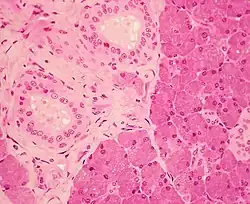

Histologie

C'est une glande exocrine, composée d'acini séreux (noyaux ronds, lumière étroite, sombre en microscopie optique en coloration HE). Elle produit l'alpha-amylase qui permet une première dégradation des sucres.

Elle possède une capsule qui émet des cloisons incomplètes à l'intérieur de la glande, délimitant des lobules. La sécrétion est excrétée par les canaux intercalaires (avec passage de Boll, qui a un épithélium cubique simple dont la lumière est plus étroite que la lumière de l'acinus, puis canal de Pflügger avec un épithélium prismatique simple), puis canaux intralobulaires (épithélium prismatique simple) s'abouchant dans les canaux interlobaires (épithélium prismatique bistratifié), et enfin se terminant au niveau du canal de Sténon (épithélium prismatique stratifié) qui s'abouche à la face interne de la joue (terminaison par un épithélium de type épidermoïde).